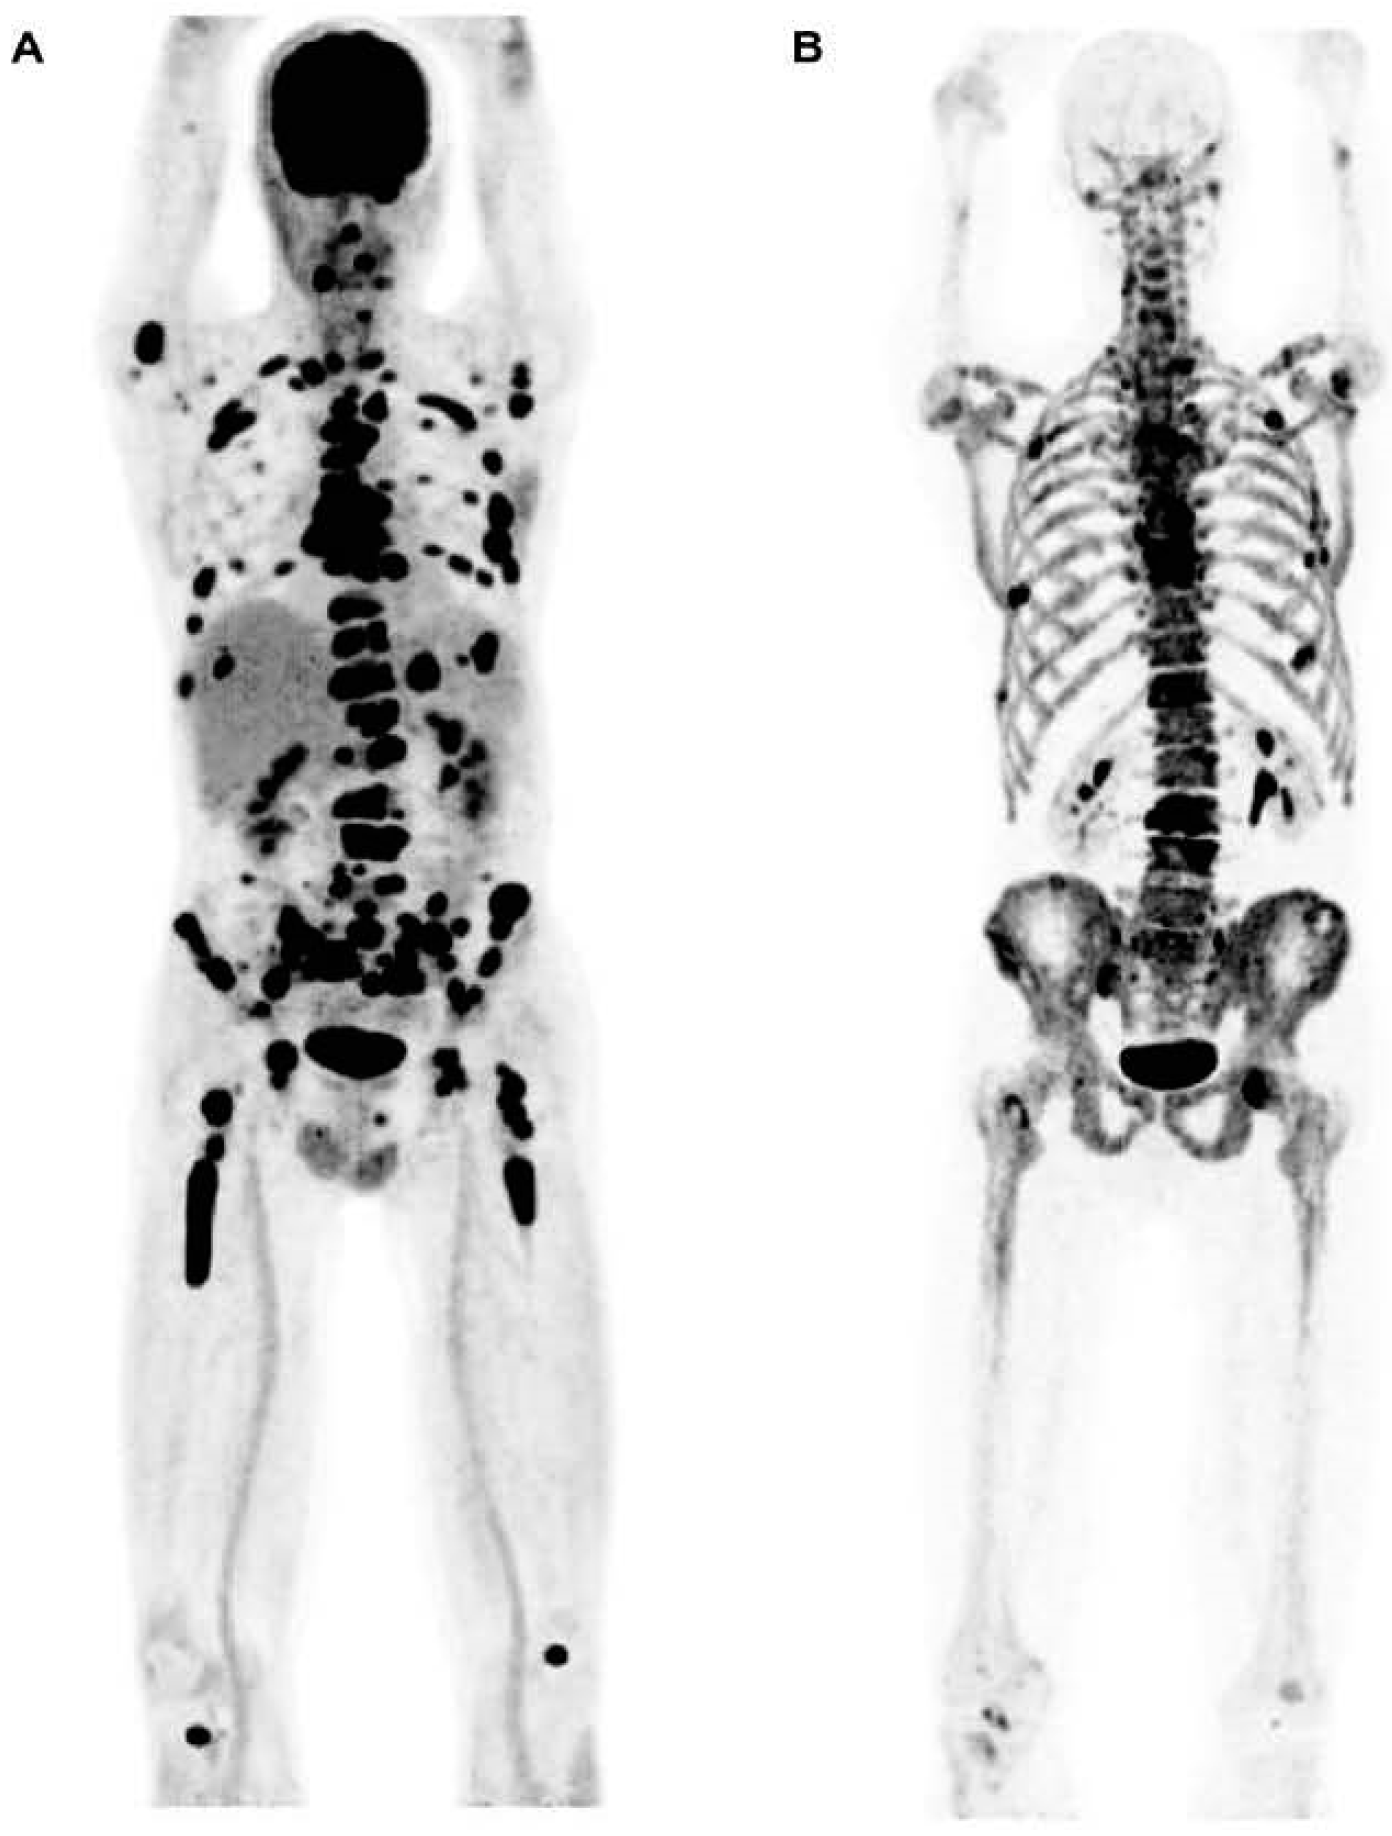

Figure 3.

This figure demonstrates the high sensitivity of [18F]FDG in detecting active MM lesions. The images present [18F]FDG PET (left) and Na[18F]F scan (right) of a 60-year-old man diagnosed with MM. The whole-body [18F]FDG PET scan reveals numerous active lesions in the skeleton and extramedullary sites (A). The whole-body Na[18F]F PET scan did not identify most of the lesions detected by [18F]FDG PET (B). The image was sourced from PMID: 31084774 (Figure 2), and permission was granted for its use.